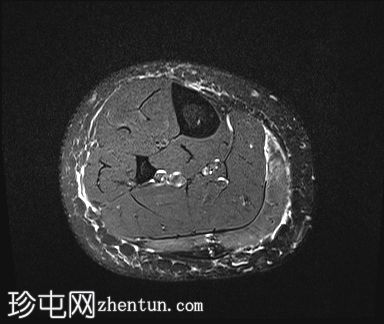

轴位

STIR序列

PD/STIR序列显示肌腱交界处附近前侧肌纤维局灶性异常高信号,符合部分肌腱拉伤/撕裂。腓肠肌内侧头与下方比目鱼肌之间可见一条细小的液性裂隙,向上延伸——典型的网球腿表现。邻近肌间筋膜间隙轻度水肿。未见全层肌肉撕裂或肌腱回缩。未见血肿或积液。腓肠肌外侧头、比目鱼肌及其余小腿肌肉信号和体积均正常。所见骨骼未见异常。